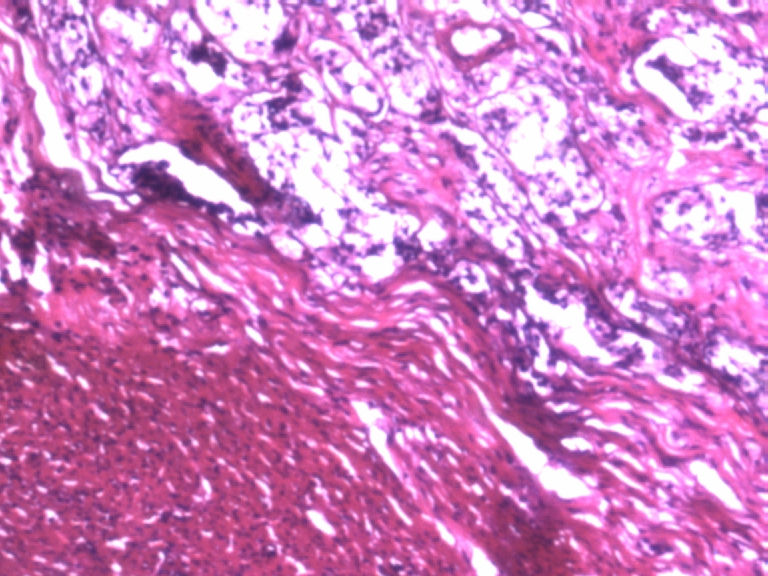

男,50岁,阑尾长7厘米,直径0.4---0.6厘米。剖开:尖端看见淡黄色区,不规则,界限欠清,0.15*0.2厘米,质中。

• 您看了吗?阑尾类癌?图1

图1

×参考诊断

考虑阑尾类癌

像类癌,有些粘液,标记一下Syn、CgA,有可能是杯状细胞类癌